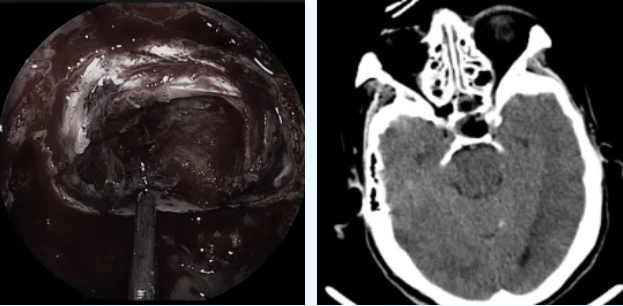

面对73岁高龄的患者,郑州大学第五附属医院神经外科三病区马建主任团队决定采用神经内镜下经鼻垂体瘤切除术——一种无需开颅的微创手术。

这项技术只需通过鼻腔的自然通道,就能直达颅内的垂体瘤区域。相比传统开颅手术,它具有创伤小、出血少、恢复快的优势。

医生使用直径仅4毫米的高清神经内镜,通过鼻孔进入,手术过程清晰地显示在高清屏幕上。肿瘤被精准完整切除,完好保护了周围的神经、血管等重要结构。

肿瘤全切,术后CT未见出血

术后第二天,李奶奶就能下地行走。复查显示她的生长激素水平已降至0.931ng/mL,恢复正常范围。

神经内镜技术作为垂体瘤治疗的重大突破,提供了超清视野,让医生能够细致观察肿瘤及其周边结构,实现精准切除。对于高龄患者,这种微创手术大大降低了风险,提高了手术安全性。